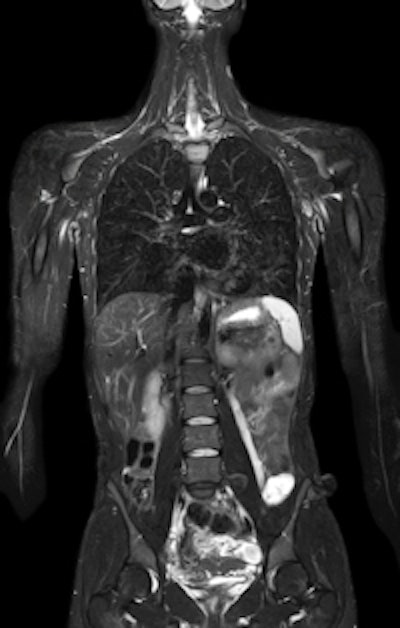

The company's new MRI family, called Ingenia, includes scanners at the 1.5-tesla and 3-tesla field strengths. The line features a new concept in signal transmission called digital broadband MR: Signals are digitized immediately at the radiofrequency (RF) coil and transmitted to the reconstruction engine via fiber-optic cable. This ensures the delivery of high-quality data without the signal loss that can occur on conventional MRI scanners, where signals travel through cables until they reach the analog-to-digital converter several feet away.

Ingenia's digital broadband MR concept results in a 40% increase in signal-to-noise ratio, according to the company. Another advantage is that it results in a channel-independent architecture for RF coils -- Ingenia scanners are currently rated for up to 128-channel coils, but Philips will be able to introduce coils with an even greater number of channels that will work on existing Ingenia systems, the company said.

![]() |

| MR image from Ingenia, courtesy of Philips. |